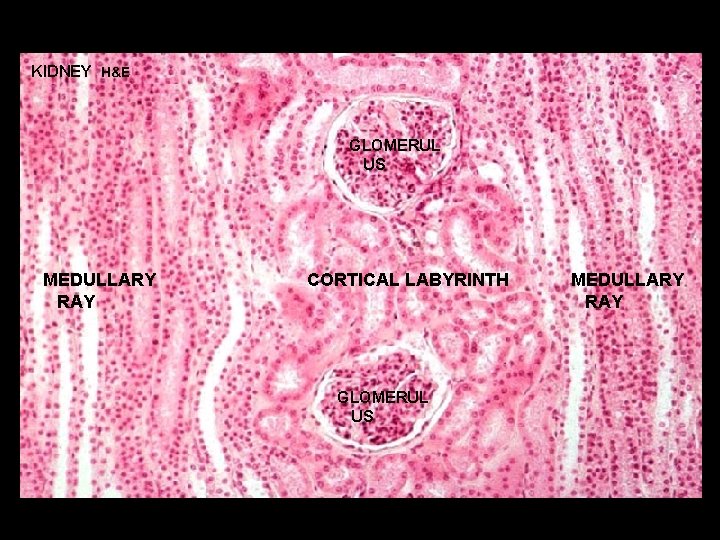

URINARY SYSTEM THE NEPHRON & COLLECTING DUCTS CORTEX: CORTICAL LABYRINTH 1 - RENAL CORPUSCLES 2 - PROXIMAL CONVOLUTED TUBULES 3 - DISTAL CONVOLUTED TUBULES MEDULLARY RAY 1 - STRAIGHT PORTIONS OF PROXIMAL TUBULE (THICK DESCENDING) 2 - STRAIGHT PORTIONS OF DISTAL TUBULE (THICK ASCENDING) 3 - COLLECTING DUCTS

KIDNEY H&E GLOMERUL US MEDULLARY RAY CORTICAL LABYRINTH GLOMERUL US MEDULLARY RAY